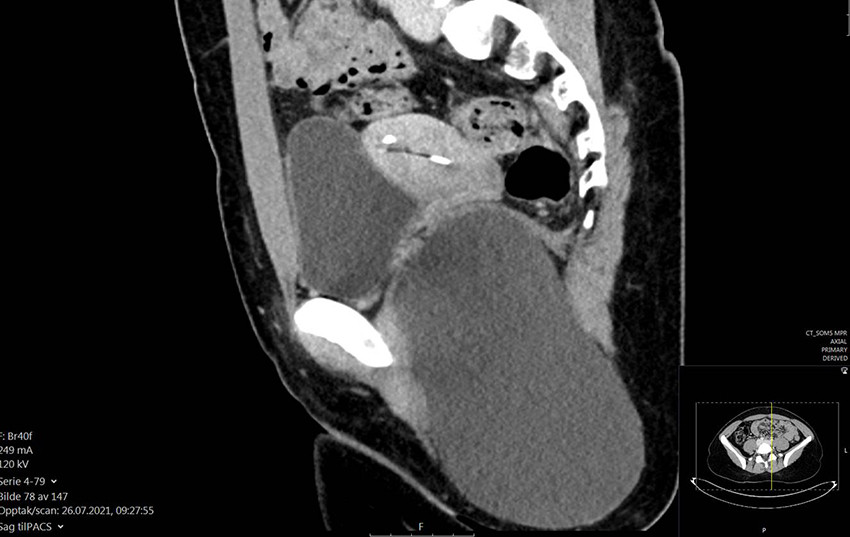

Bildet viser en unilokulær cyste med en glatt og jevn innside som inneholder rikelig med kuleformede talg- og hårelementer (bilde 1). Den ble fjernet in toto og helt uten ruptur. Sagittalt CT-bilde av bekken tatt preoperativt viser en stor, unilokulær cystisk oppfylning i venstre fossa ischiorectalis, som gir lett kranial forskyvning av musculus levator ani (bilde 2). Lesjonen ble målt til 16,3 × 9,8 × 8,8 cm. Histologisk undersøkelse postoperativt avdekket en cyste kledd av plateepitel med underliggende hårsekker med arrector pili-muskler samt talg- og svettekjertler (bilde 3).

Det histologiske bildet, sammenholdt med anatomisk lokalisasjon og radiologi, var forenlig med en dermoid cyste i fossa ischiorectalis. Dermoide cyster er benigne og oppstår som en feilutvikling når ektodermale elementer fanges langs de embryonale linjene i fosterlivet og insidensen hos barn er ca. 3 per 100 000 (1, 2). 70 % av tilfellene oppdages innen fem års alder, men noen lesjoner oppdages ikke før i voksen alder (1). Histologisk er cystene bygget opp av en epidermal og dermislignende cystevegg med svettekjertler og hårstrukturer (1, 2). Cystene oppstår vanligst på hodet og i nakkeregionen, men kan forekomme over hele kroppen og vokser vanligvis sakte (3). Indisert behandling er kirurgisk ekstirpasjon av cysten (1).